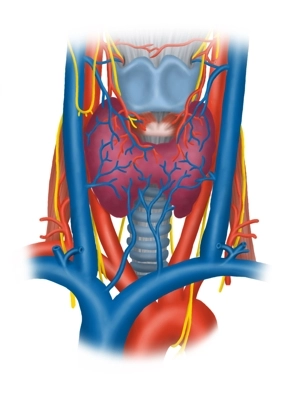

Vasos sanguíneos

La A. carotis communis se divide en el borde superior del cartílago tiroides a la altura de su seno carotídeo (receptores para la presión arterial y quimiorreceptores para gases sanguíneos) en su rama interna y externa y discurre previamente de forma inmediata lateral en la vaina carotídea junto a la tráquea y el esófago hacia craneal. Aquí toca como gran vaso los lóbulos tiroideos derecho e izquierdo. Del seno sigmoide del cráneo surge la V. jugularis interna, que recoge la sangre del cráneo y cuello, dirigiéndose hacia caudal inicialmente adosada a la A. carotis interna en la vagina carotica, luego discurre más lateralmente y envuelve lateralmente la A. carotis communis así como el N. vagus (N. X).

Nervios

Además del N. vagus y su rama superior al laringe (N. laryngeus superior → M. cricothyroideus anterior, así como mucosa de la mitad superior del laringe) se encuentra en la zona de la glándula tiroides lateralmente, descendiendo desde arriba, la ansa cervicalis profunda (radix superior e inferior, de C1-C3) para la inervación de los tres músculos mencionados del triángulo cervical anterior y el N. transversus colli (de C2/3, inervación cutánea, platisma).